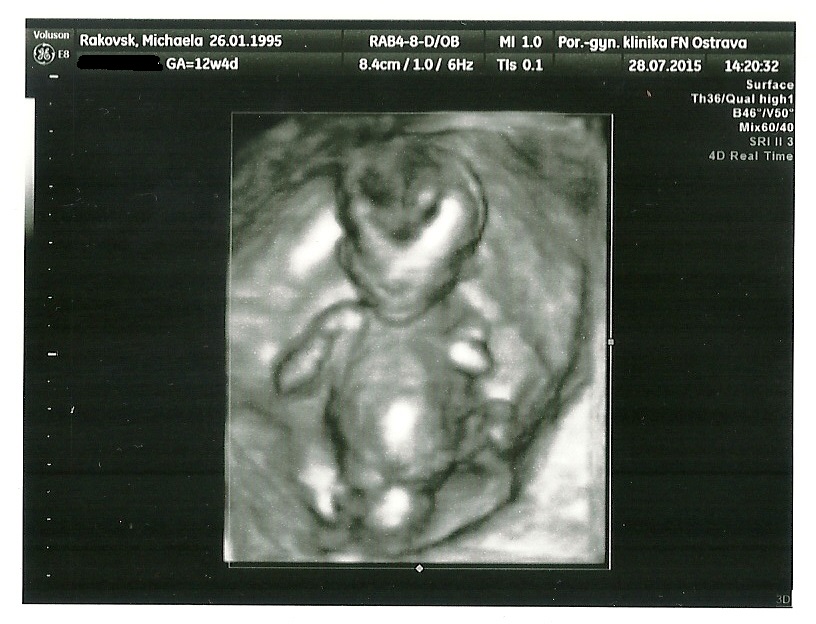

13tt a náš první 3D na 1. screeningu :P Doktorovi se tenhle pohled moc nelíbil, ale mamince se líbí její marťánek moc a tak si vzala i fotečku :P :*